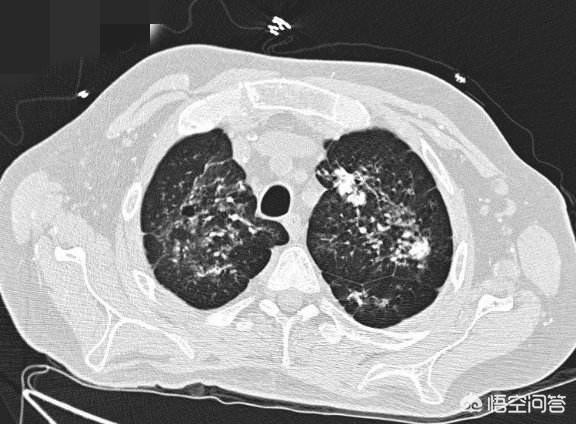

En général, des foyers striés limités ou des foyers calcifiés indiquent qu'il s'agit d'une lésion ancienne, et la figure suivante est une image CT typique d'un patient présentant des foyers calcifiés dans la partie apicale du poumon gauche.